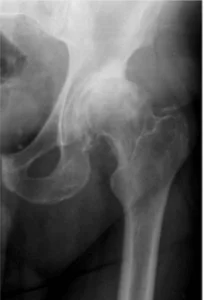

O que é a artrose no quadril?

A artrose é uma doença de origem multifatorial que leva à degeneração da cartilagem articular, afetando todos os componentes da articulação. É um processo lento, progressivo e incapacitante, com alta prevalência na população adulta.

A artrose do quadril é uma das causas mais frequentes de artrose dos membros inferiores, resultando em um impacto negativo na qualidade de vida das pessoas, aumentando o risco de mortalidade e problemas cardiovasculares.